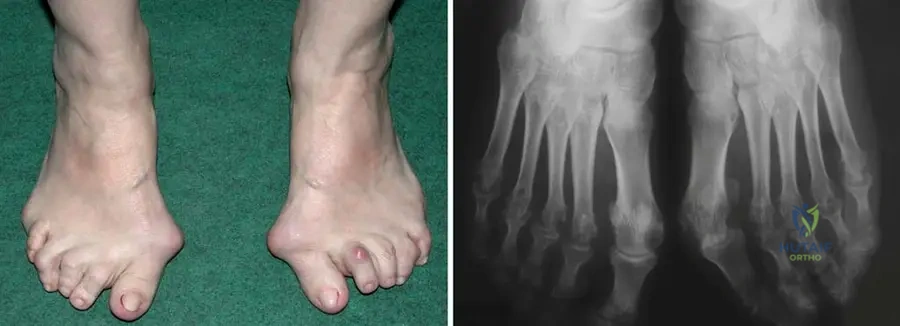

A 60-year-old female with long-standing rheumatoid arthritis complains of significant foot pain and difficulty wearing shoes. Physical examination reveals severe forefoot deformities, including hallux valgus, hammer toes, and a flat foot appearance. Radiographs confirm fibular deviation of the toes, metatarsophalangeal (MTP) joint destruction, and erosions.

View Answer & Explanation

Correct Answer: D

Rationale: The described deformities—hallux valgus, hammer toes, MTP joint destruction, flat foot, and fibular deviation of toes—are classic and severe forefoot manifestations of rheumatoid arthritis. These result from chronic synovitis, ligamentous laxity, and bone erosion. The main distractor, B, describes a pes cavus deformity, which is the opposite of the flat foot often seen in RA, and claw toes are different from hammer toes, though both involve toe contractures.